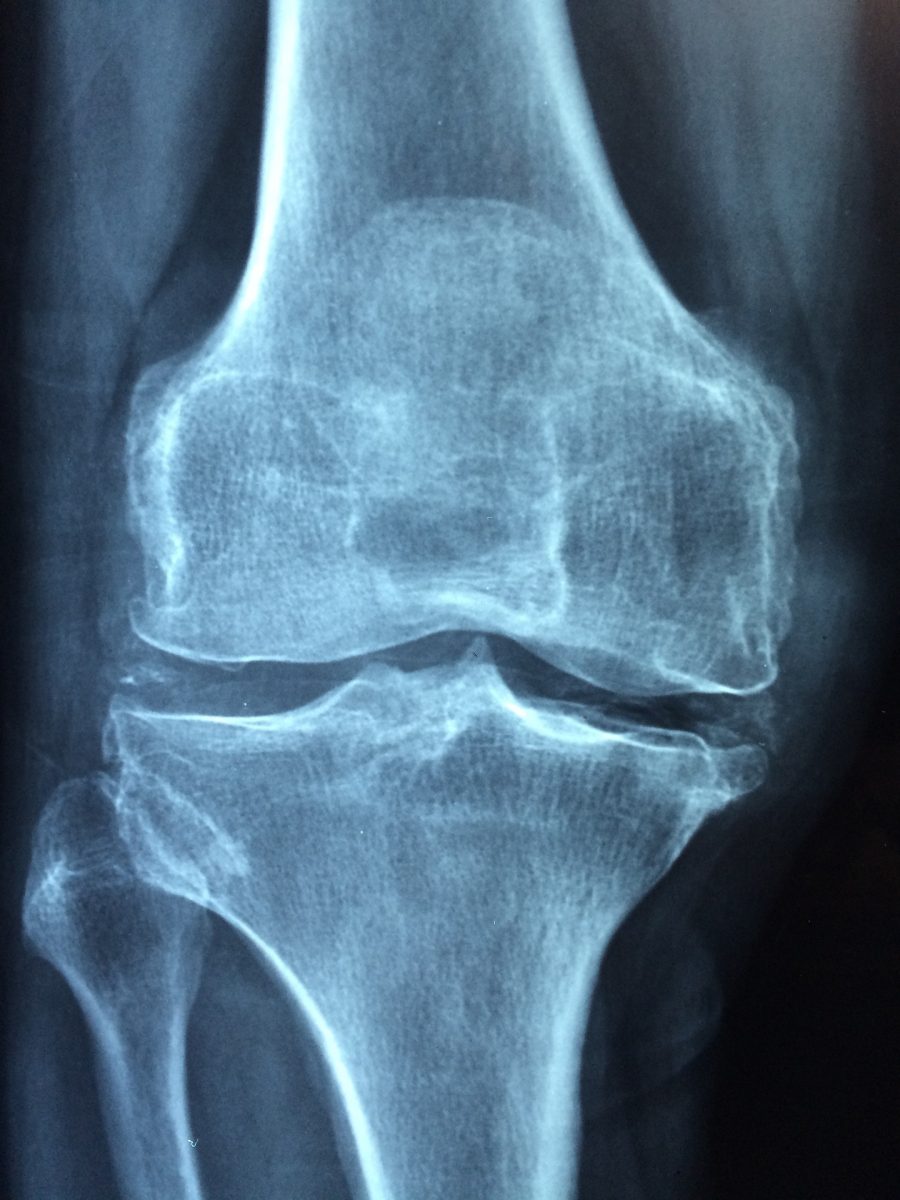

Az emberi ízületekben található egy csúszós, rugalmas szövet, az úgynevezett porc, ami az artikuláló csontok végét borítja. Ha ez a védőréteg sérülés vagy öregedés következtében elvész, a csont a csonton kezd őrlődni jelentős fájdalmat okozva.

Sajnos a porcsérülés kifejezetten gyakorinak számít és ritkán gyógyul meg magától. Ez további károkat okozhat az ízületben, ami krónikus ízületi gyulladáshoz vezethet, ami az egyik leggyakoribb ízületi gyulladás és a mozgásban korlátozó betegségek egyik vezető oka világszerte. A 60 évesnél idősebb emberek 10–15 százaléka rendelkezik bizonyos fokú osteoarthritisszel. Eddig nem nagyon volt erre gyógymód, de talán úton a segítség.